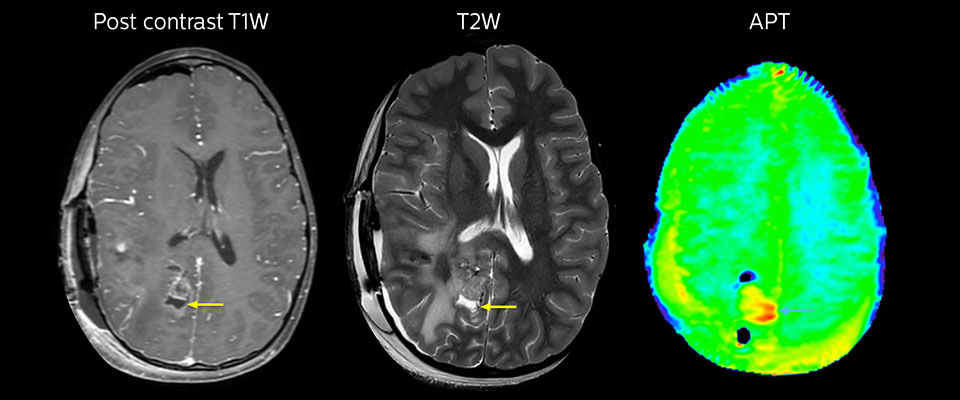

MRI with APT post resection

Immediately post resection MRI was again performed. T2-weighted and postcontrast T1-weighted images are quite inconclusive for distinguishing residual tumor tissue from postoperative tissue changes. On the APT image some high signal is still seen, which would suggest residual tumor tissue.